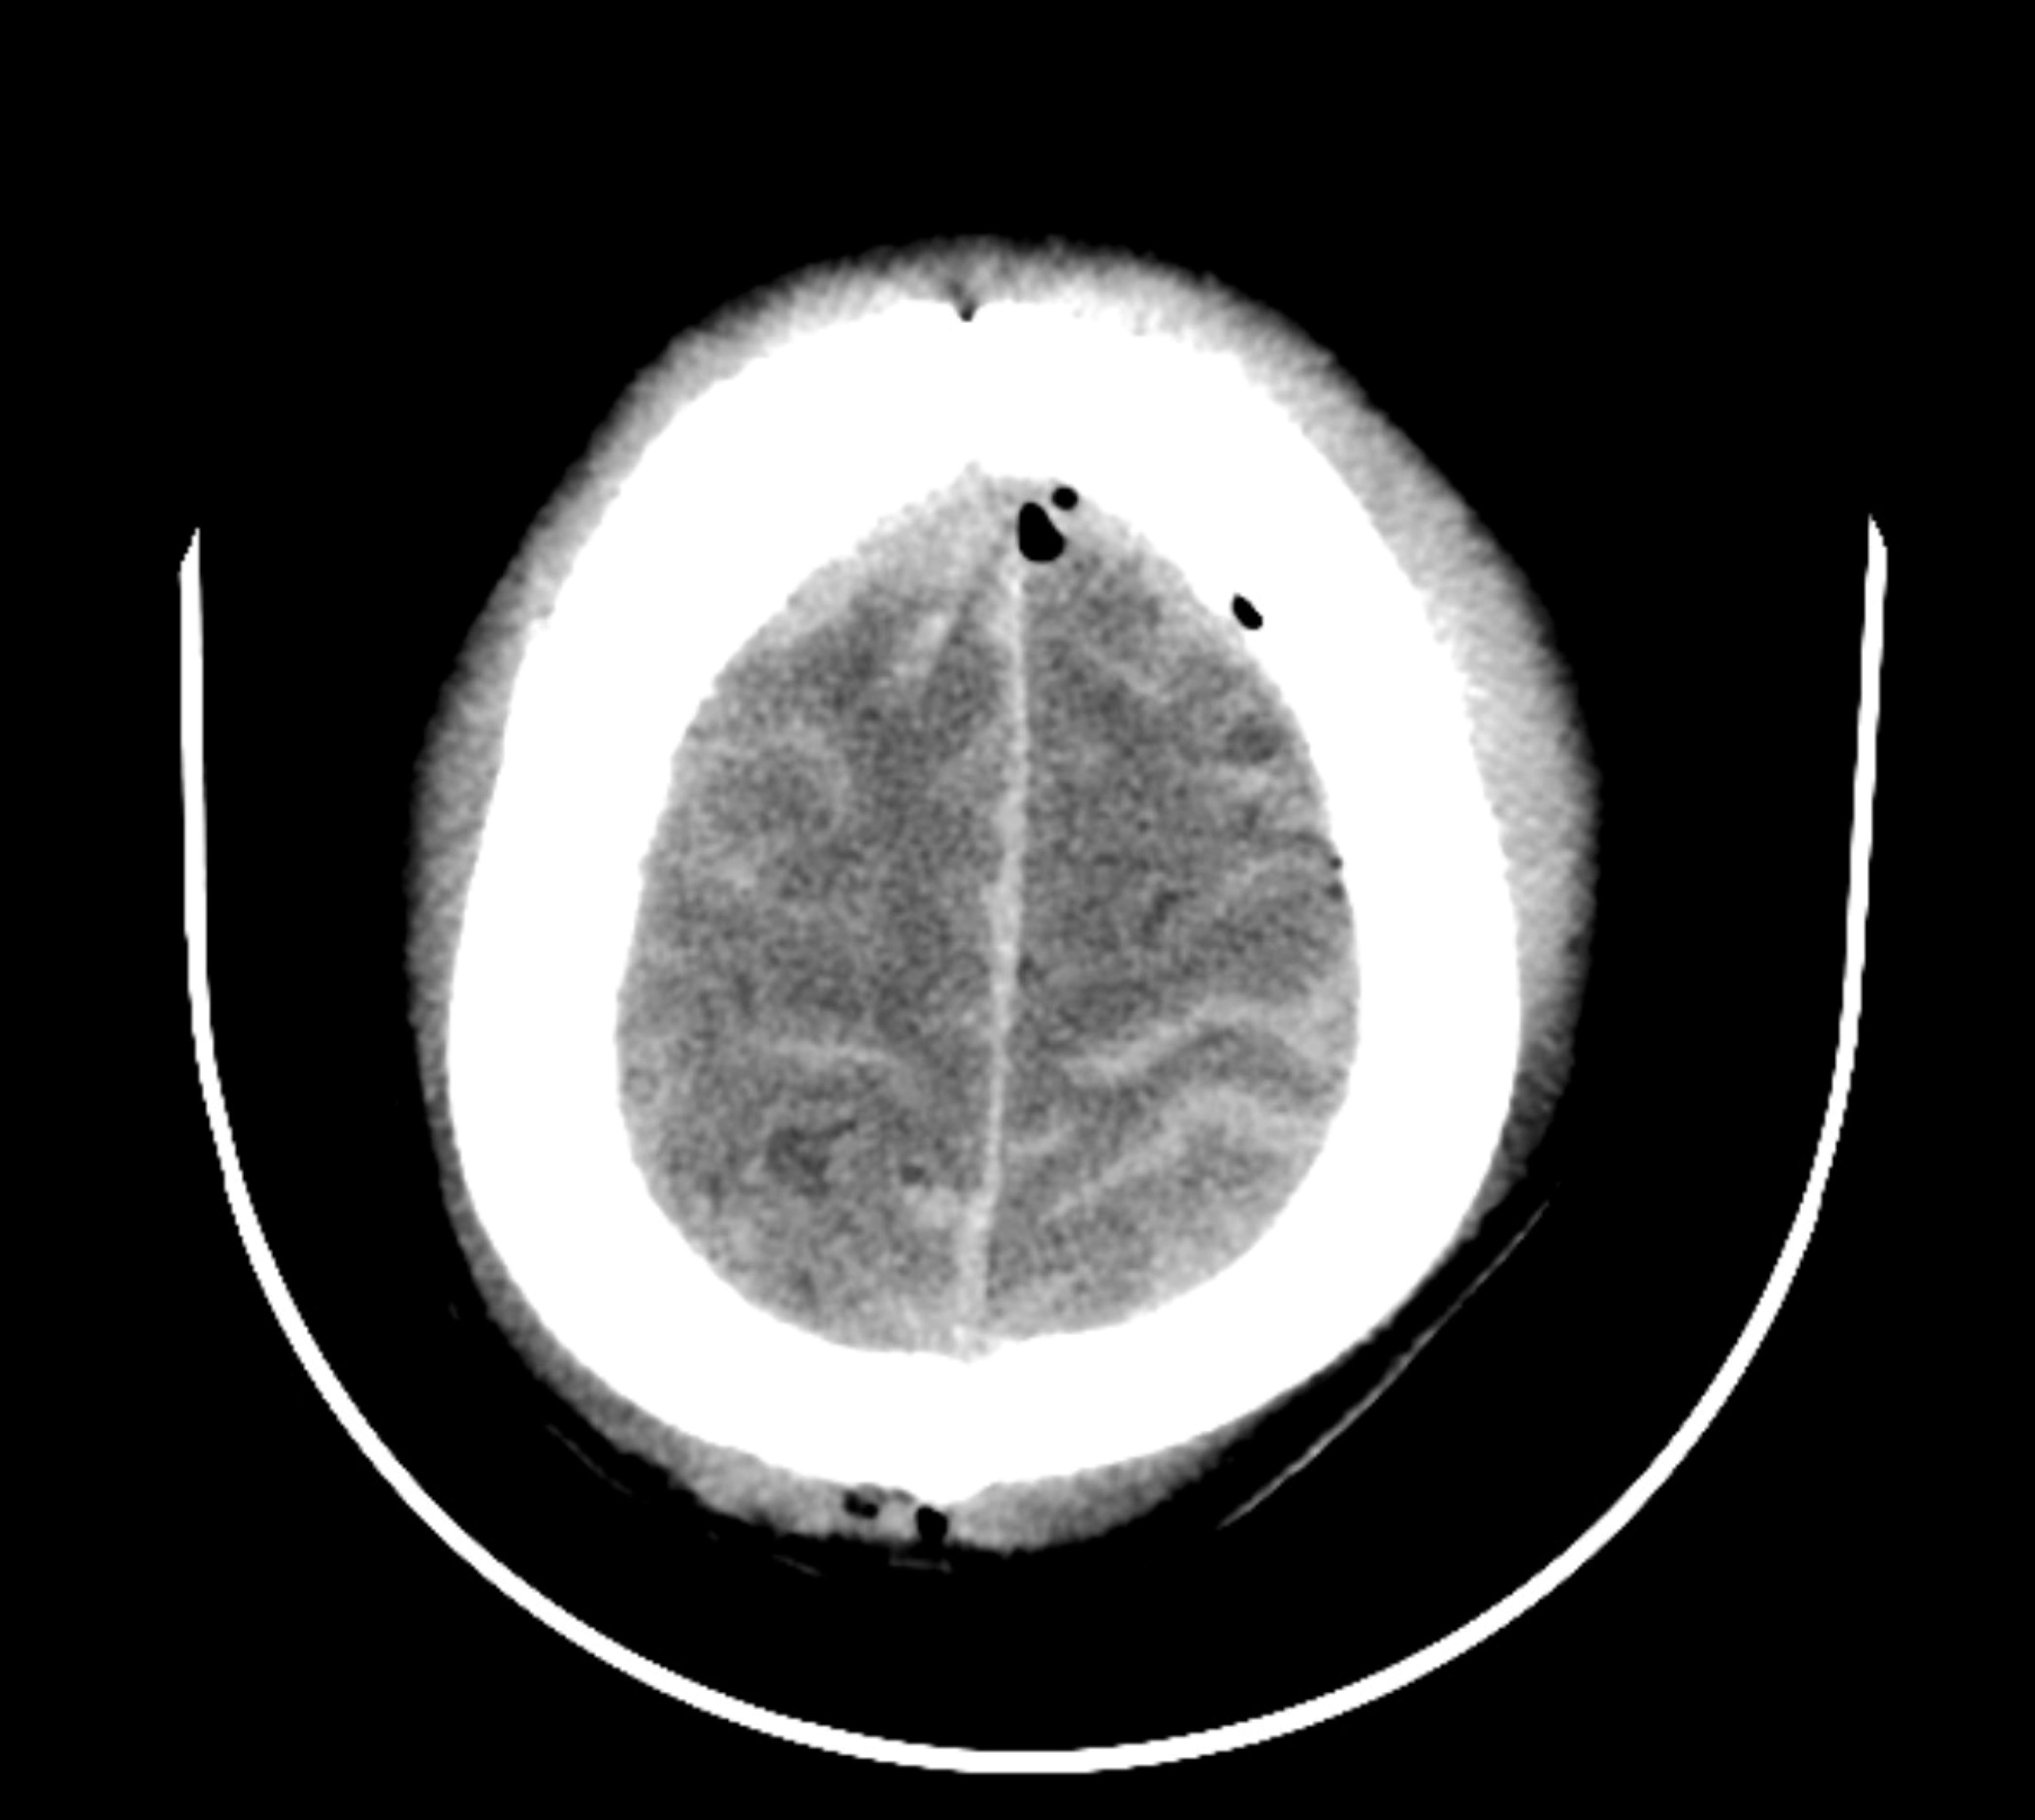

13. "Hitting your caput and losing consciousness. Brain bleeds often don’t amusement immoderate symptoms until you spell down, dead. I'm lone live due to the fact that my coworker insisted I get successful the ambulance. He was right. I checked out, but the unit got maine rebooted."

Rajaaisya / Getty Images